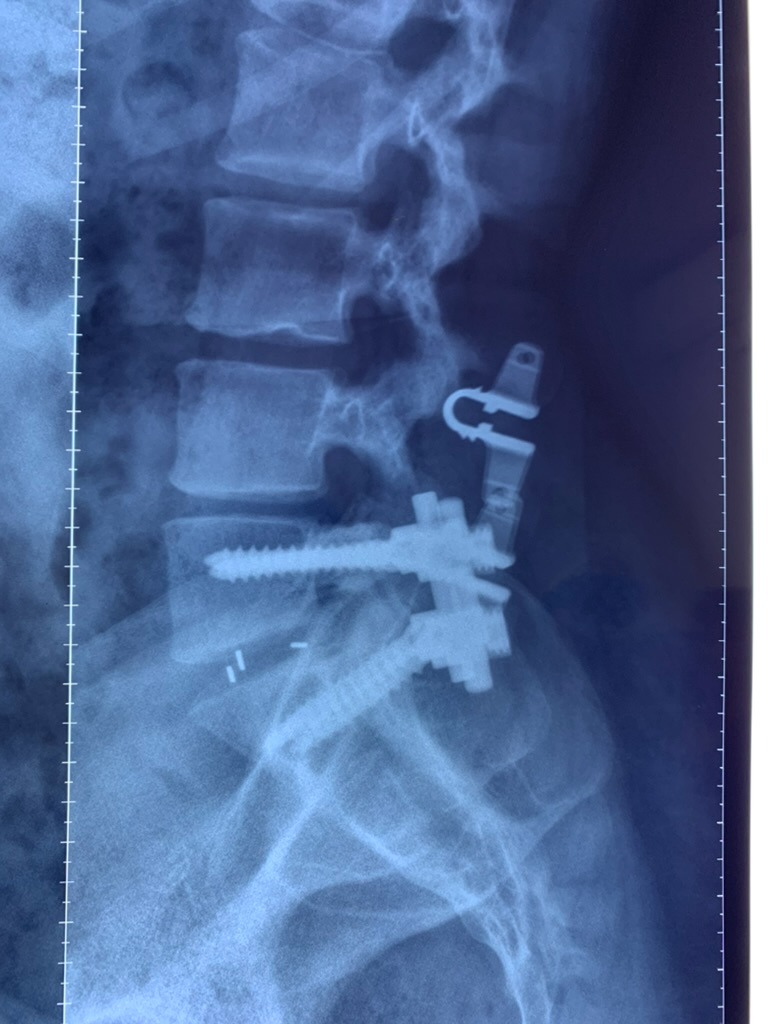

SURGERIES

RESULTS